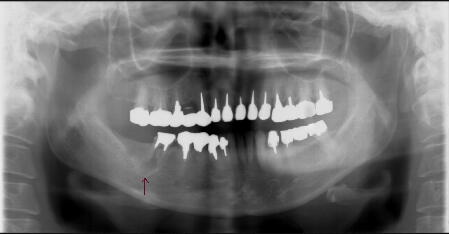

(1)不十分な根管(神経の通っていた管)治療が原因で右下の顎が腫れています。(↑病巣

が極めて大きい) ![]() ![]() ![]() ![]()

当初は抜歯を考慮しました(上左図)が、根の治療を丁寧に行うことによって、半年後には

ほぼ問題の無い程度(上右図)にまで骨が修復され十分に機能が回復されました。